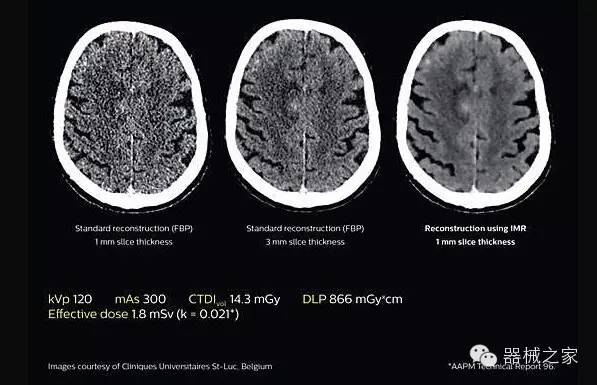

透過數(shù)字化影真芯片DAS系統(tǒng)、球面微平板探測(cè)器技術(shù)和濾線柵技術(shù)等硬件技術(shù),整體提高探測(cè)器成像的能力,奠定低劑量條件下高清成像的基礎(chǔ);

應(yīng)用目前業(yè)界領(lǐng)先的新一代星光平臺(tái)iDose4 Premium及基于迭代基礎(chǔ)的O一MAR去除金屬偽影技術(shù),達(dá)成微量輻射下零偽影的高清晰成像;

2.腦部顯影